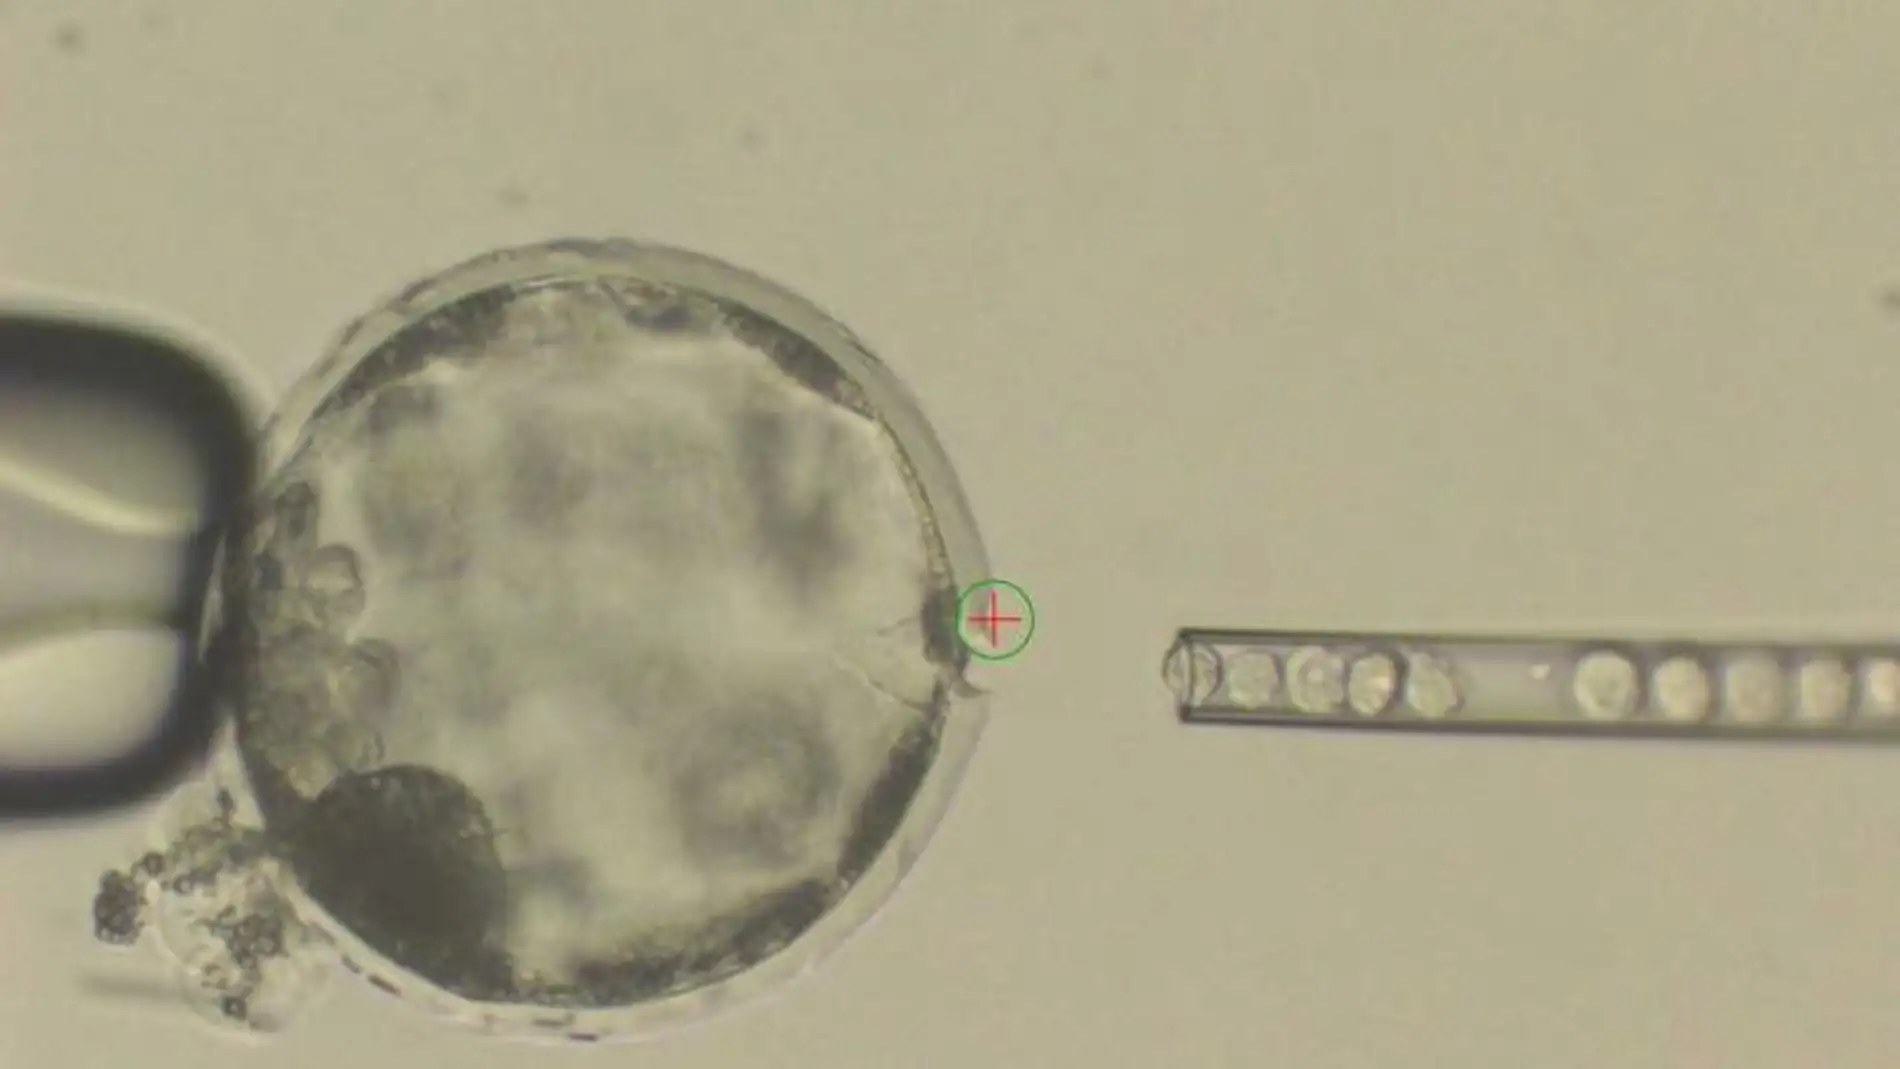

Los primeros experimentos se llevaron cabo con ratones, inyectando células madre de rata en embriones de ratón y dejándolos madurar. Mediante herramientas de edición de genoma, como CRISPR, se ha trabajado con embriones fertilizados.

En esos embriones se eliminaron genes involucrados en el crecimiento de órganos como los ojos, el corazón o el páncreas y se rellenaron esos huecos con su equivalente en genes de rata. El resultado fue un animal quimérico, un ratón híbrido con ojos, corazón y páncreas de rata.

Se usaron distintos tipos de células humanas para comprobar cual tenía una mayor tasa de supervivencia. Las que mostraron mayores posibilidades para su desarrollo y mayor supervivencia fueron las llamadas células pluripotentes.

Las células supervivientes formaron un embrión quimérico entre humano y cerdo que se implantó en cerdas y así estudiar su desarrollo durante tres o cuatro semanas, tiempo suficiente para evitar problemas éticos y entender cómo se mezclan las células de cerdo y humanas.